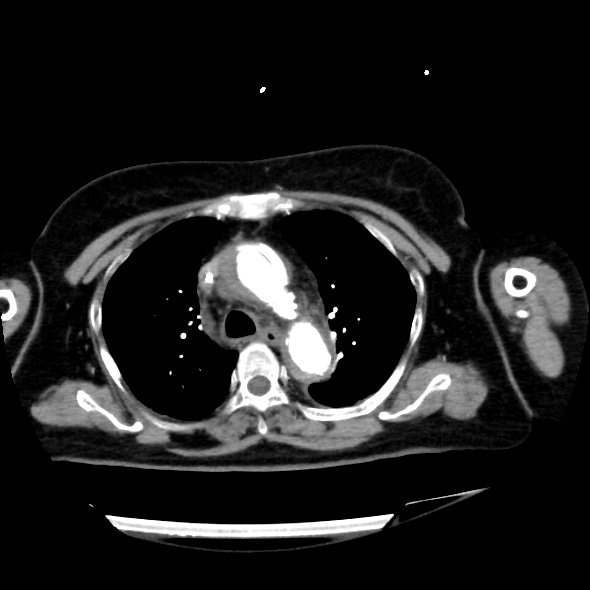

急性大動脈解離の造影CT

70歳代、女性、54kg、Stanford A型急性大動脈解離

症例は70歳台女性。胸背部痛を主訴に近医を受診し、単純CTを撮像したところ、Stanford A型急性大動脈解離を認めたため、加療目的に当院へ転院搬送となった。既往に慢性腎臓病があり、Cre 2.43mg/dL、eGFR 15.7と高度腎機能障害を認めたが、リスクベネフィットを検討した結果、術前精査のために造影CTが施行された。解離の範囲や造影剤のエントリー部位を同定することができた。

造影CTは急性大動脈解離の診断において最重要の検査であり、真腔と偽腔の描出、エントリー部位や偽腔内血栓の有無を評価できる。また、MPRや3D再構成を用いることで大動脈全体や末梢血管の状態を把握でき、手術やInterventional Radiologyによる手技前の血管解剖評価にも有用である。さらに、造影効果不良域の検出、ULP(ulcer-like projection)、臓器梗塞も早期に発見可能である。このように、造影CTは非侵襲的で短時間で行えるため、緊急疾患である急性大動脈解離に最適なモダリティといえる。一方で注意点は、造影剤アレルギーや腎障害など副作用への配慮、適切なプロトコル設計が求められる点である。造影CTは急性大動脈解離の確定診断と治療方針決定に不可欠であり、有効性を活かしつつリスク管理を徹底して施行する必要がある。

CT技術や撮像プロトコル設定について